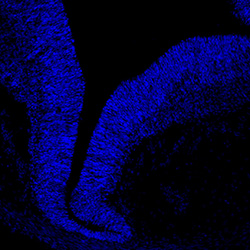

DAPI

13PCW human midbrain

GFAP